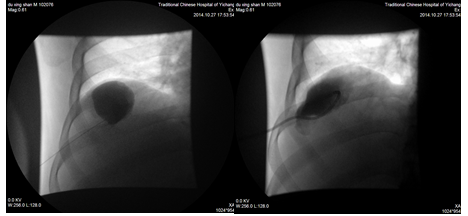

典型病例、患者、男、55岁,因发现巨大肝囊肿,在我院介入科行CT引导下穿刺引流+硬化治疗术后恢复良好。